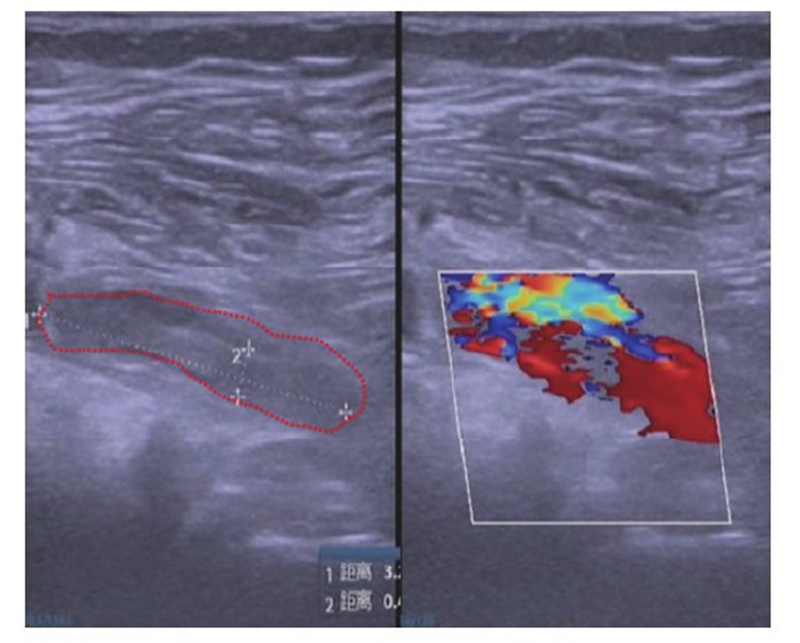

术后第1天复查下肢血管彩超及实验室检查凝血功能,发现腘动脉血栓形成及凝血功能异常(图4~5),患者未诉 不适。体检发现足背动脉搏动较对侧弱,皮温略低,末梢血氧饱和度90%。请显微外科及心血管内科会诊后,心血管内科建议切开取栓,将病情告知患者及家属后行急诊取栓术。术中可见腘动脉分叉近端约2cm大小的半月板缝合袢将腘动脉捆扎,但仍有血流通过(图6),切开血管,取出血栓,取出半月板缝合袢,松开止血带,见血流好,在显微镜下修复腘动脉,再次松开止血带,见动脉搏动良好,无漏血,足背动脉搏动好,末梢血氧饱和度99%,手术完毕。患者术后第1天开始主动活动,双侧皮温一致,未诉患肢疼痛,复查右下肢动静脉彩超示右侧动静脉血流通畅(图7),术后24个月随访患者右下肢活动功能良好,双下肢无明显肿胀,双侧皮温一致,小腿腿围基本一致,患者McMurray征阴性,前抽屉试验阴性,膝关节稳定性良好,活动度良好。

图4 术后 第1天彩超可见一条索状与心率一致的搏动性阴影(红色虚线区 域),提示右侧腘动脉血流减缓